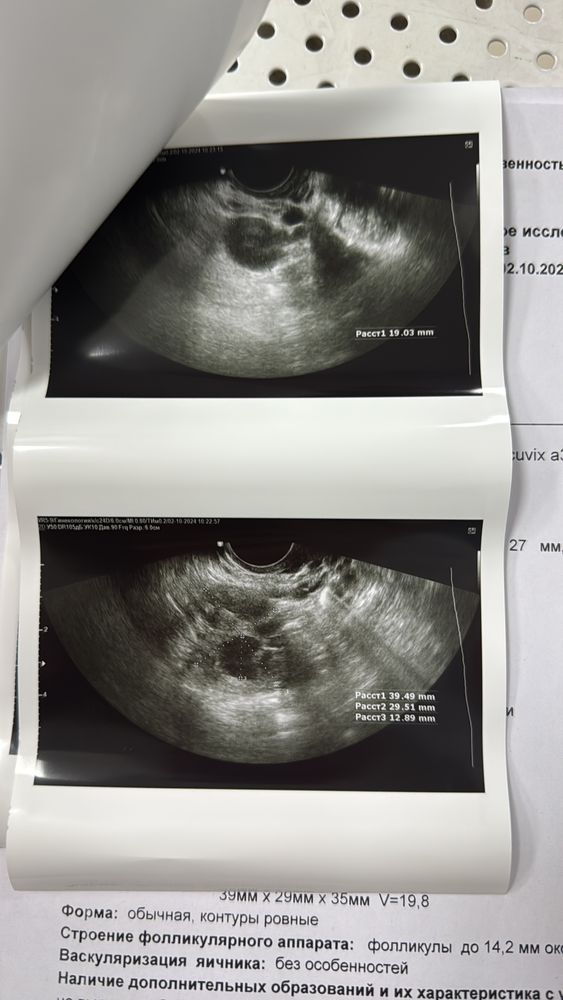

Ландыш Габдуллова в Зачатие год Узи Заключение УЗИ Проверьте пожалуйста, была ли овуляция 28 день цикла, месячные нерегулярные Посмотрите еще 20 записей на эту тему Отменить Ответить Нет ощущений На какое дпо делали УЗИ ? Чаты Беременных Выберите чат: Январята-2026 Февралята-2026 Мартята-2026 Апрелята-2026 Майчата-2026 Июнята-2026 Июлята-2026 Августята-2026